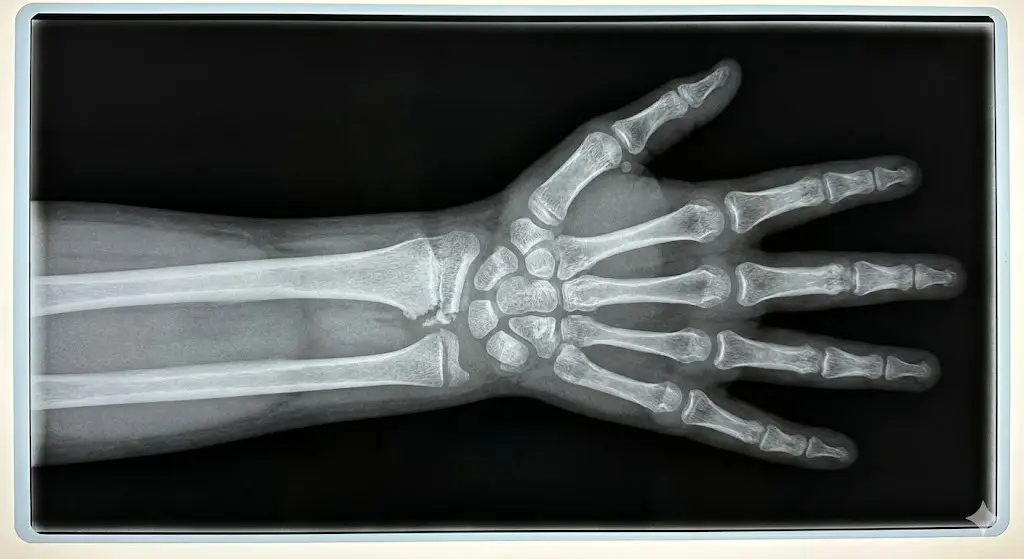

• Röntgenkuvien tulkinta: Lasten luissa on kasvulinjoja, kasvutumakkeita ja rustoisia osia, jotka poikkeavat aikuisten luista. Tämän vuoksi kuvien tulkinta vaatii kokenutta silmää, jotta murtuma erotetaan esim. normaalista kasvulinjasta.

Jos murtuma ulottuu kasvulinjaan, on toisinaan tilannetta seurattava tarkemmin. Kasvulinja on alue, josta luu kasvaa pituutta, ja vaurio tällä alueella voi vaikuttaa luun normaaliin kasvuun.

• Jälkitarkastus: Kasvulinjamurtumissa otetaan toisinaan uusi röntgenkuva noin 6 kuukauden kohdalla.

• Mitä seurataan? Kuvalla varmistetaan, ettei kasvulinja ole luutunut murtuman kohdalta ennenaikaisesti umpeen, mikä voisi johtaa kasvuhäiriöön.